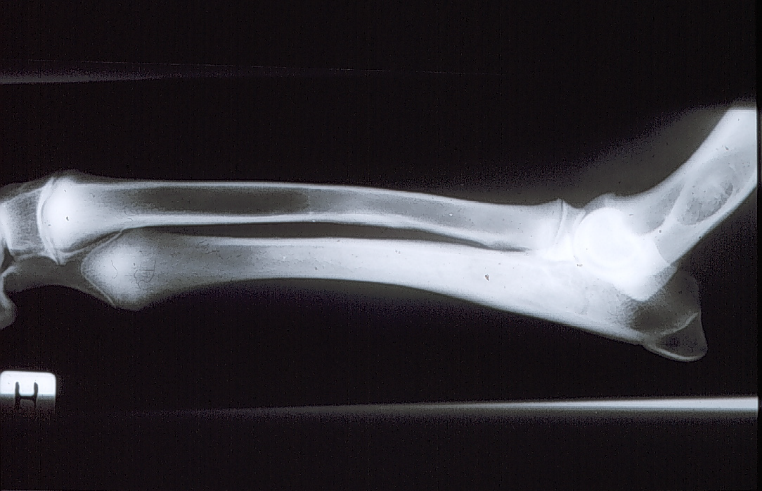

Eosinofil panostitis

Karakteristisk: formindsket knogledensitet

Ætiologi: ukendt.

Patogenese: knogledannelse i cavum medulare omkring foramen nutritium, hvilket gør at knoglen ikke får næring og derved ses nedsat densitet.